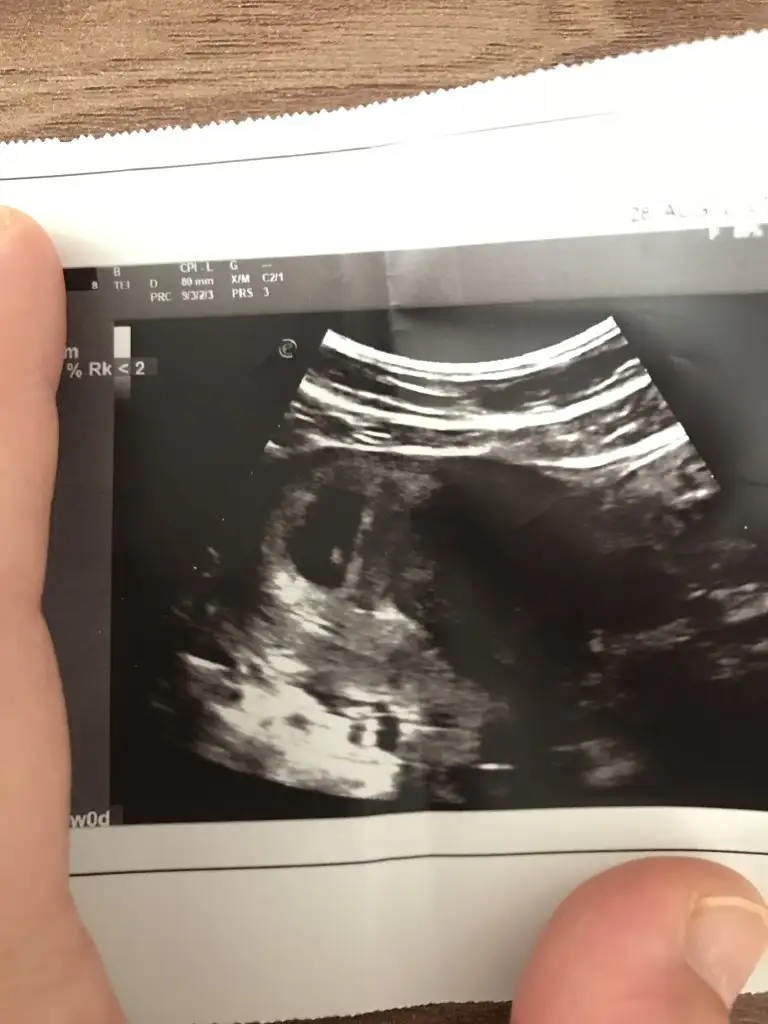

Bebeğiniz ters mi duruyor bana mı öyle geliyorBana da yorum yapar mısınız

Evet ama doktor yine de cinsiyeti söyledi nasıl anladı onu da bilmiyorumBebeğiniz ters mi duruyor bana mı öyle geliyor

Sizin tahmin ne 15 haftalık fotoğraf buBebeğiniz ters mi duruyor bana mı öyle geliyor

Başka bir ultrason varsa bakabilir miyim kıza benziyor sankiSizin tahmin ne 15 haftalık fotoğraf bu

Başka bir ultrason varsa önceki haftalara dair daha net görünenEvet ama doktor yine de cinsiyeti söyledi nasıl anladı onu da bilmiyorum

Biri 8 haftalık iken diğeri ise 14 haftadaBaşka bir ultrason varsa önceki haftalara dair daha net görünen

Kıza benziyor canımBiri 8 haftalık iken diğeri ise 14 haftada

Doktorum da öyle dedi bu ay gittiğimde kesin netlik kazanacak bakalımKıza benziyor canım